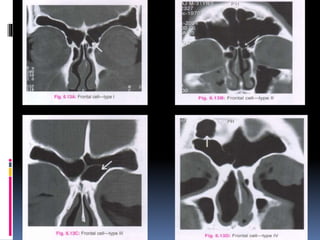

 The anterior ethmoid cells may migrate into

frontal recess area where they are then named

Frontal cells.

 I –Type I frontal cell (a single air cell above agger

nasi)

 II –Type II frontal cell (a series of air cells above

agger nasi but below the orbital roof)

 III –Type III frontal cell (this cell extends into the

frontal sinus but is contiguous with agger nasi )

 IV –Type IV frontal cell lies completely within

the frontal sinus (Loner cell)

TYPES OF FRONTAL CELLS-